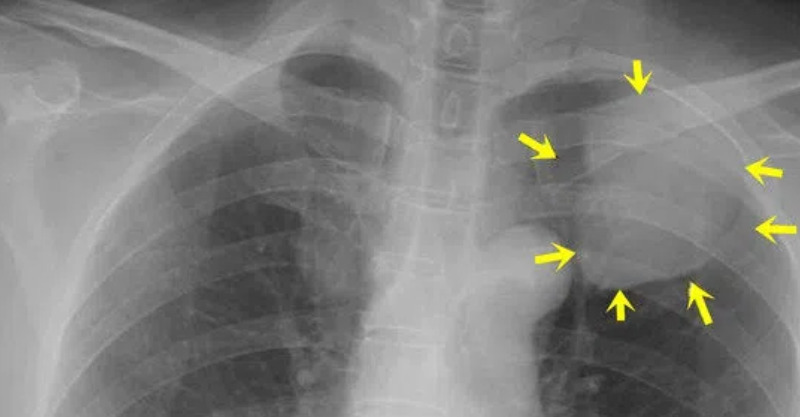

在臨床看來,肺癌出現癥狀、進入發展期後,最為典型的表現就是以下四類:

1、刺激性乾咳

明明呼吸道內沒有異物存在,但偏偏自己總感覺有東西刺激支氣管,反覆出現了刺激性嗆咳、乾咳等癥狀,有時甚至是咳出了泡沫痰,且經過止咳藥物控制後,咳嗽癥狀不但沒有緩解、反而是變得越來越頻繁,這就可能與肺部癌變有關。

因為癌腫本就是出現在肺部的異物,它會對支氣管產生強烈刺激,導致患者出現咳嗽癥狀。根據臨床掌握的資料來看,有超過50%的肺癌患者首發癥狀就是咳嗽;

2、痰中帶血

之前可能僅僅只是嗆咳或乾咳,沒有痰液咳出,近段時間不僅開始咳痰,痰液中還有少量肉眼可見的血絲,這也是肺部癌變的表現。

因為癌腫表面分佈的血管扭曲、沒有分佈規律,它們相當之脆弱。在咳嗽的過程中,會對腫瘤產生強烈刺激和壓迫,導致腫瘤表面的血管破裂出血,患者就會因此出現痰中帶血、少量咯血等癥狀;

3、聲音嘶啞

在絕大部分情況下,聲嘶的出現都和說話、吸煙酗酒、咽喉炎等問題有關,在經過休息、調整生活狀態或用藥後即可緩解。

而相反的,如果近期突然出現了聲音嘶啞、進展十分迅速、用藥後無緩解,這也可能與肺癌有關。

因為肺癌在持續增長的過程中,容易對喉返神經產生壓迫,導致患者左側聲帶麻痹,繼而出現聲嘶癥狀;

4、胸悶氣短